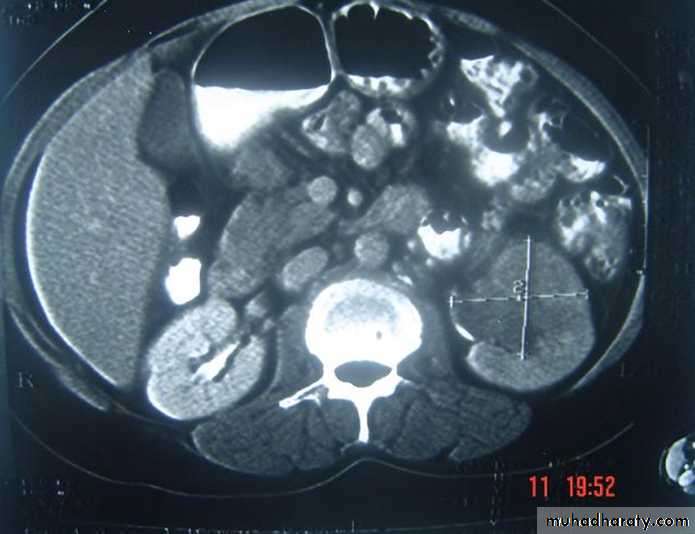

IVU :-

* Nephrogram shows filling defect which is irregular .* Distracted PCS .

* Hydronephrosis.

* Amputation & missing calyces .

* Large non-functioning kidney .

CT